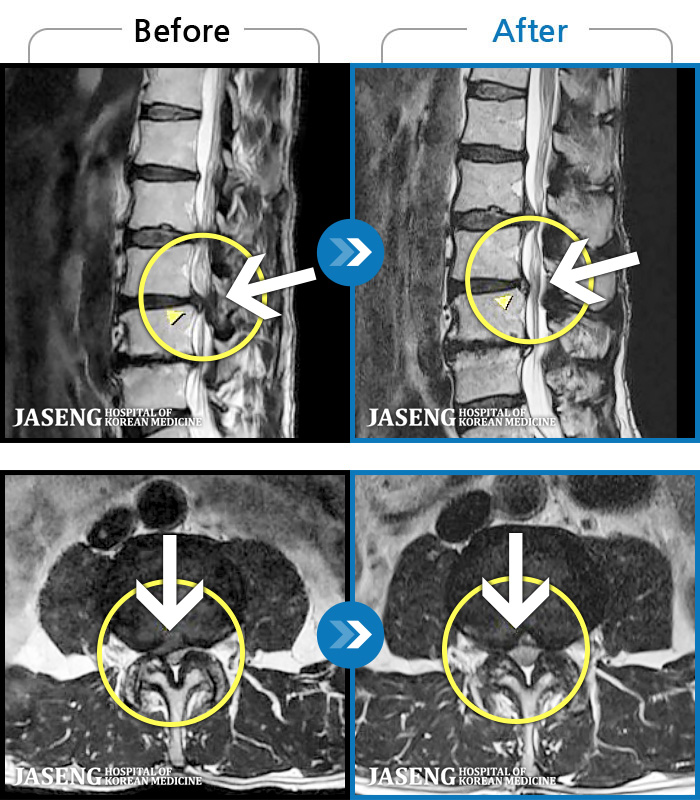

- MRI ġ

MRI ġ

1,299 MRI ũ ʸ Ȯϼ.